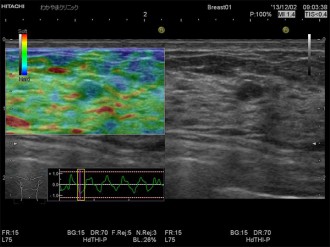

エラストグラフィとは、超音波検査でしこりの硬さを画像化する技術です。

その変形の程度を色で表したものがエラストグラフィで、周囲よりも硬い部分は青く表示されます。

がん組織は、周辺組織より硬い場合が多く、しこりの硬さを知ることは診断の一つの重要な情報となります。

乳がん検査の一つである超音波検査にエラストグラフィを組み合わせることで、硬さという診断に有用な情報を付加し、検査を受ける方にとっても負担の少ない優しい検査がおこなえます。